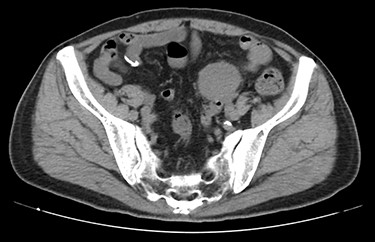

A 70-year-old man underwent robot-assisted laparoscopic cystectomy with bladder replacement for bladder cancer. The pathological diagnosis was stage 0 (Tis, N0, M0). Nine months after the operation, no plain computed tomography (CT) findings indicated cancer recurrence. Thirteen months after the operation, contrast-enhanced CT showed a well-defined intra-abdominal mass, up to 50 × 40 mm in size, with heterogeneous enhancement. The tumor was in contact with the small intestine (Fig. 1). Magnetic resonance imaging (MRI) revealed an isolated mass with hypointensity on T1-weighted images and mild hyperintensity on T2-weighted images (Fig. 2a and b). Fluorine-18 fluorodeoxyglucose positron emission tomography CT (FDG-PET/CT) revealed mild FDG uptake in the tumor, with a maximum standardized uptake value (SUV max) of 3.4 (Fig. 3). Based on these findings, bladder cancer recurrence or mesenchymal tumors derived from the small intestine or mesentery were suspected. The tumor showed a rapid growth trend and required immediate therapeutic intervention. However, a differential diagnosis based on the imaging findings alone was difficult to achieve. Therefore, we decided to perform a diagnostic surgery to identify the intra-abdominal tumor.

Contrast-enhanced CT showed a well-defined mass in contact with the small intestine that had heterogeneous enhancement.